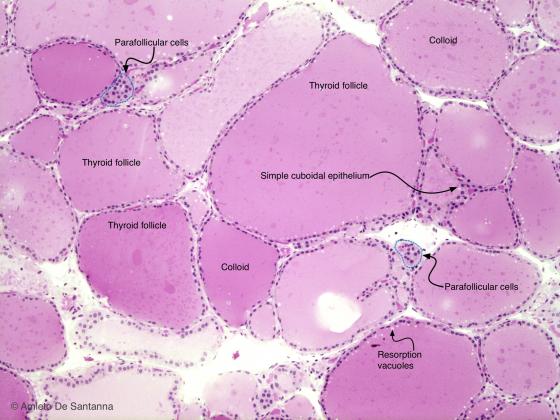

Cuboidal Cell -Thyroid

Cuboid shaped Cell with Central Round Nucleus-PKK